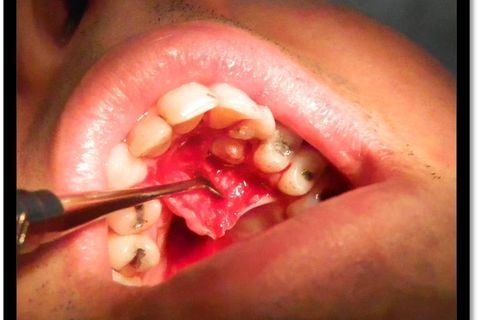

Paciente com palato atresico, com indicacação de ortodontia, apresentou o 23 e 18 incluso e impactado. Optou-se por fazer remoção em duas etapas, primeiro o 23 e após 15 dias o 18. Usou-se como anestésico mepiadri 2% 3 tubetes infiltrativa por vestibular e palatina, descolamento por lingual de 13 á 24 devido a atresia. Houve exposição do plexo da fossa incisiva, mas com sangramento dentro da normalidade, fez-se acesso endodontico e utilizou-se uma lima endodontica após a divulsão dos tecidos para remoção do dente com menor dano ao paciente.

Fotos do caso